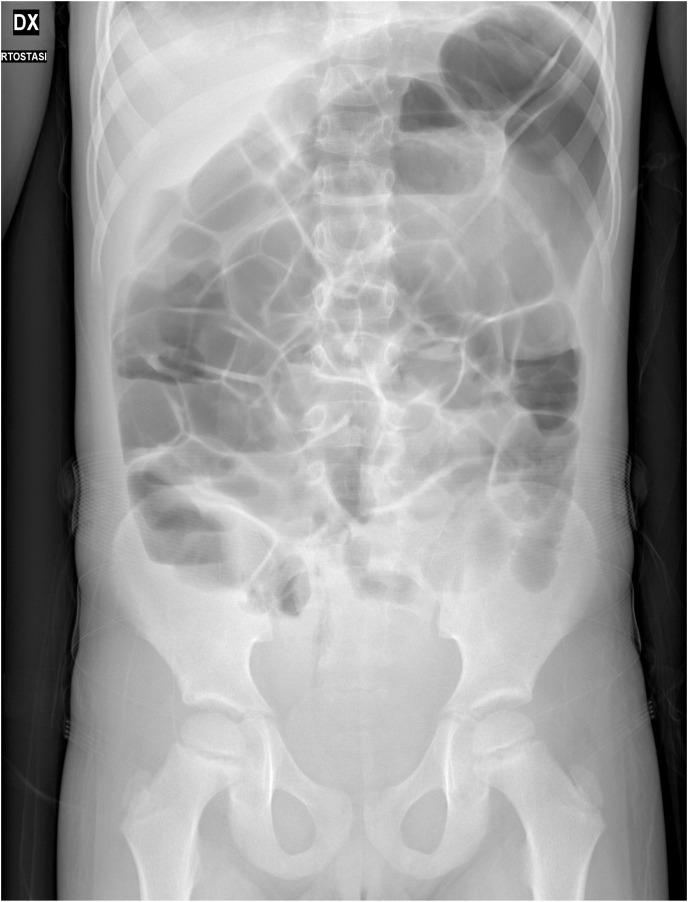

BACKGROUND/PURPOSE: Multisystem inflammatory syndrome in children (MIS-C) is a potentially life-threatening condition occurring 2-6 weeks after Coronavirus disease 2019 (COVID-19) in previously healthy children and adolescents, characterized by clinical and laboratory evidence of multiorgan inflammation. We reported the case of a 6-year-old child presented with acute abdomen and then diagnosed with MIS-C. In addition, to better portray this new entity, we performed a systematic review of MIS-C gastrointestinal features and particularly on those mimicking surgical emergencies.

Our patient was initially assessed by the surgical team due to his query acute abdomen. Following the diagnosis of MIS-C with myocarditis, intravenous methylprednisolone (2 mg/Kg/day) and intravenous immunoglobulins (2 gr/Kg single infusion) were promptly started, leading to clinical improvement. According to our literature search, patients with MIS-C have a high rate of severe abdominal symptoms resembling surgical emergencies (appendicitis, obstruction, etc.) and a not negligible number of those patients have been surgically explored with variable findings.

We encourage pediatric surgeons in the upcoming months of COVID-19 pandemic to evaluate myocardial function prior to surgical abdominal exploration. In children with query acute abdomen, MIS-C should be promptly ruled out in order to avoid unnecessary surgeries that could worsen the already frail outcome of this new syndrome. Nevertheless, it should be considered that MIS-C might well encompass complications (e.g. appendicitis, segmental intestinal ischemia) which need swift surgical treatment.